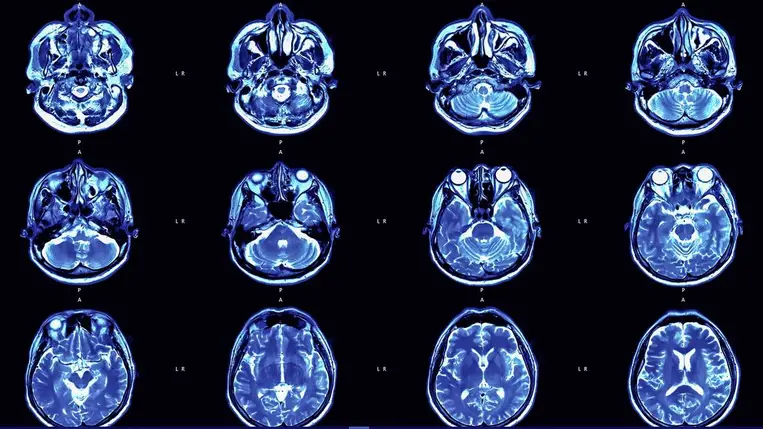

Egy új kutatás szerint a koronavírus-járvány önmagában – a fertőzéstől függetlenül – is hatással lehetett az emberi agy öregedésére.

A Magyar Molekuláris Medicina Kiválósági Központ szegedi Neuron Fiziológia és Terápia kutatócsoportja szerint az idegsejtek hatékonyságromlása okozza a mozgás és gondolkodás lassulását öregkorban.

Akár napi egy pohár bor is megváltoztathatja az agy szerkezetét.